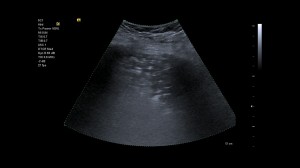

Caption foto: Pneumonie asociata COVID-19. Examinare realizata in unitatea de primiri urgente utilizand sonda convexa. Ultrasunetele releva zone largi de consolidari in partea superioara posterioara stanga, precum si semne de bronhograma aericaInfectia cu SARS-CoV-2 afecteaza initial micile alveole de la nivelul periferiei plamanilor. Ca o regula, leziunile sunt localizate foarte aproape de pleura, prin urmare intr-o zona ce poate fi foarte bine vizualizata de un ecograf. In ecografia pulmonara diagnosticul este bazat pe artifacte, care sunt aparente, fenomene interferante in radiologie, CT sau rezonanta magnetica. Pentru COVID-19 au fost identificate urmatoarele artifacte caracteristice:

- Linia orizontala bogata in ecouri corespunzatoare pleurei viscerale (linia pleurei) apare ingrosata si neregulata

- Liniile B cu modele diferite, inclusiv linii focale, multifocale și confluente

- Consolidare (acumulari de lichid si / sau tesut in alveolele pulmonare care impiedica schimbul de gaze) cu modele variate, incluzand mici linii multifocale, non-translobare si translobare

- Aparitia liniilor A in faza de recuperare

- Efuziunile pleurale sunt rare